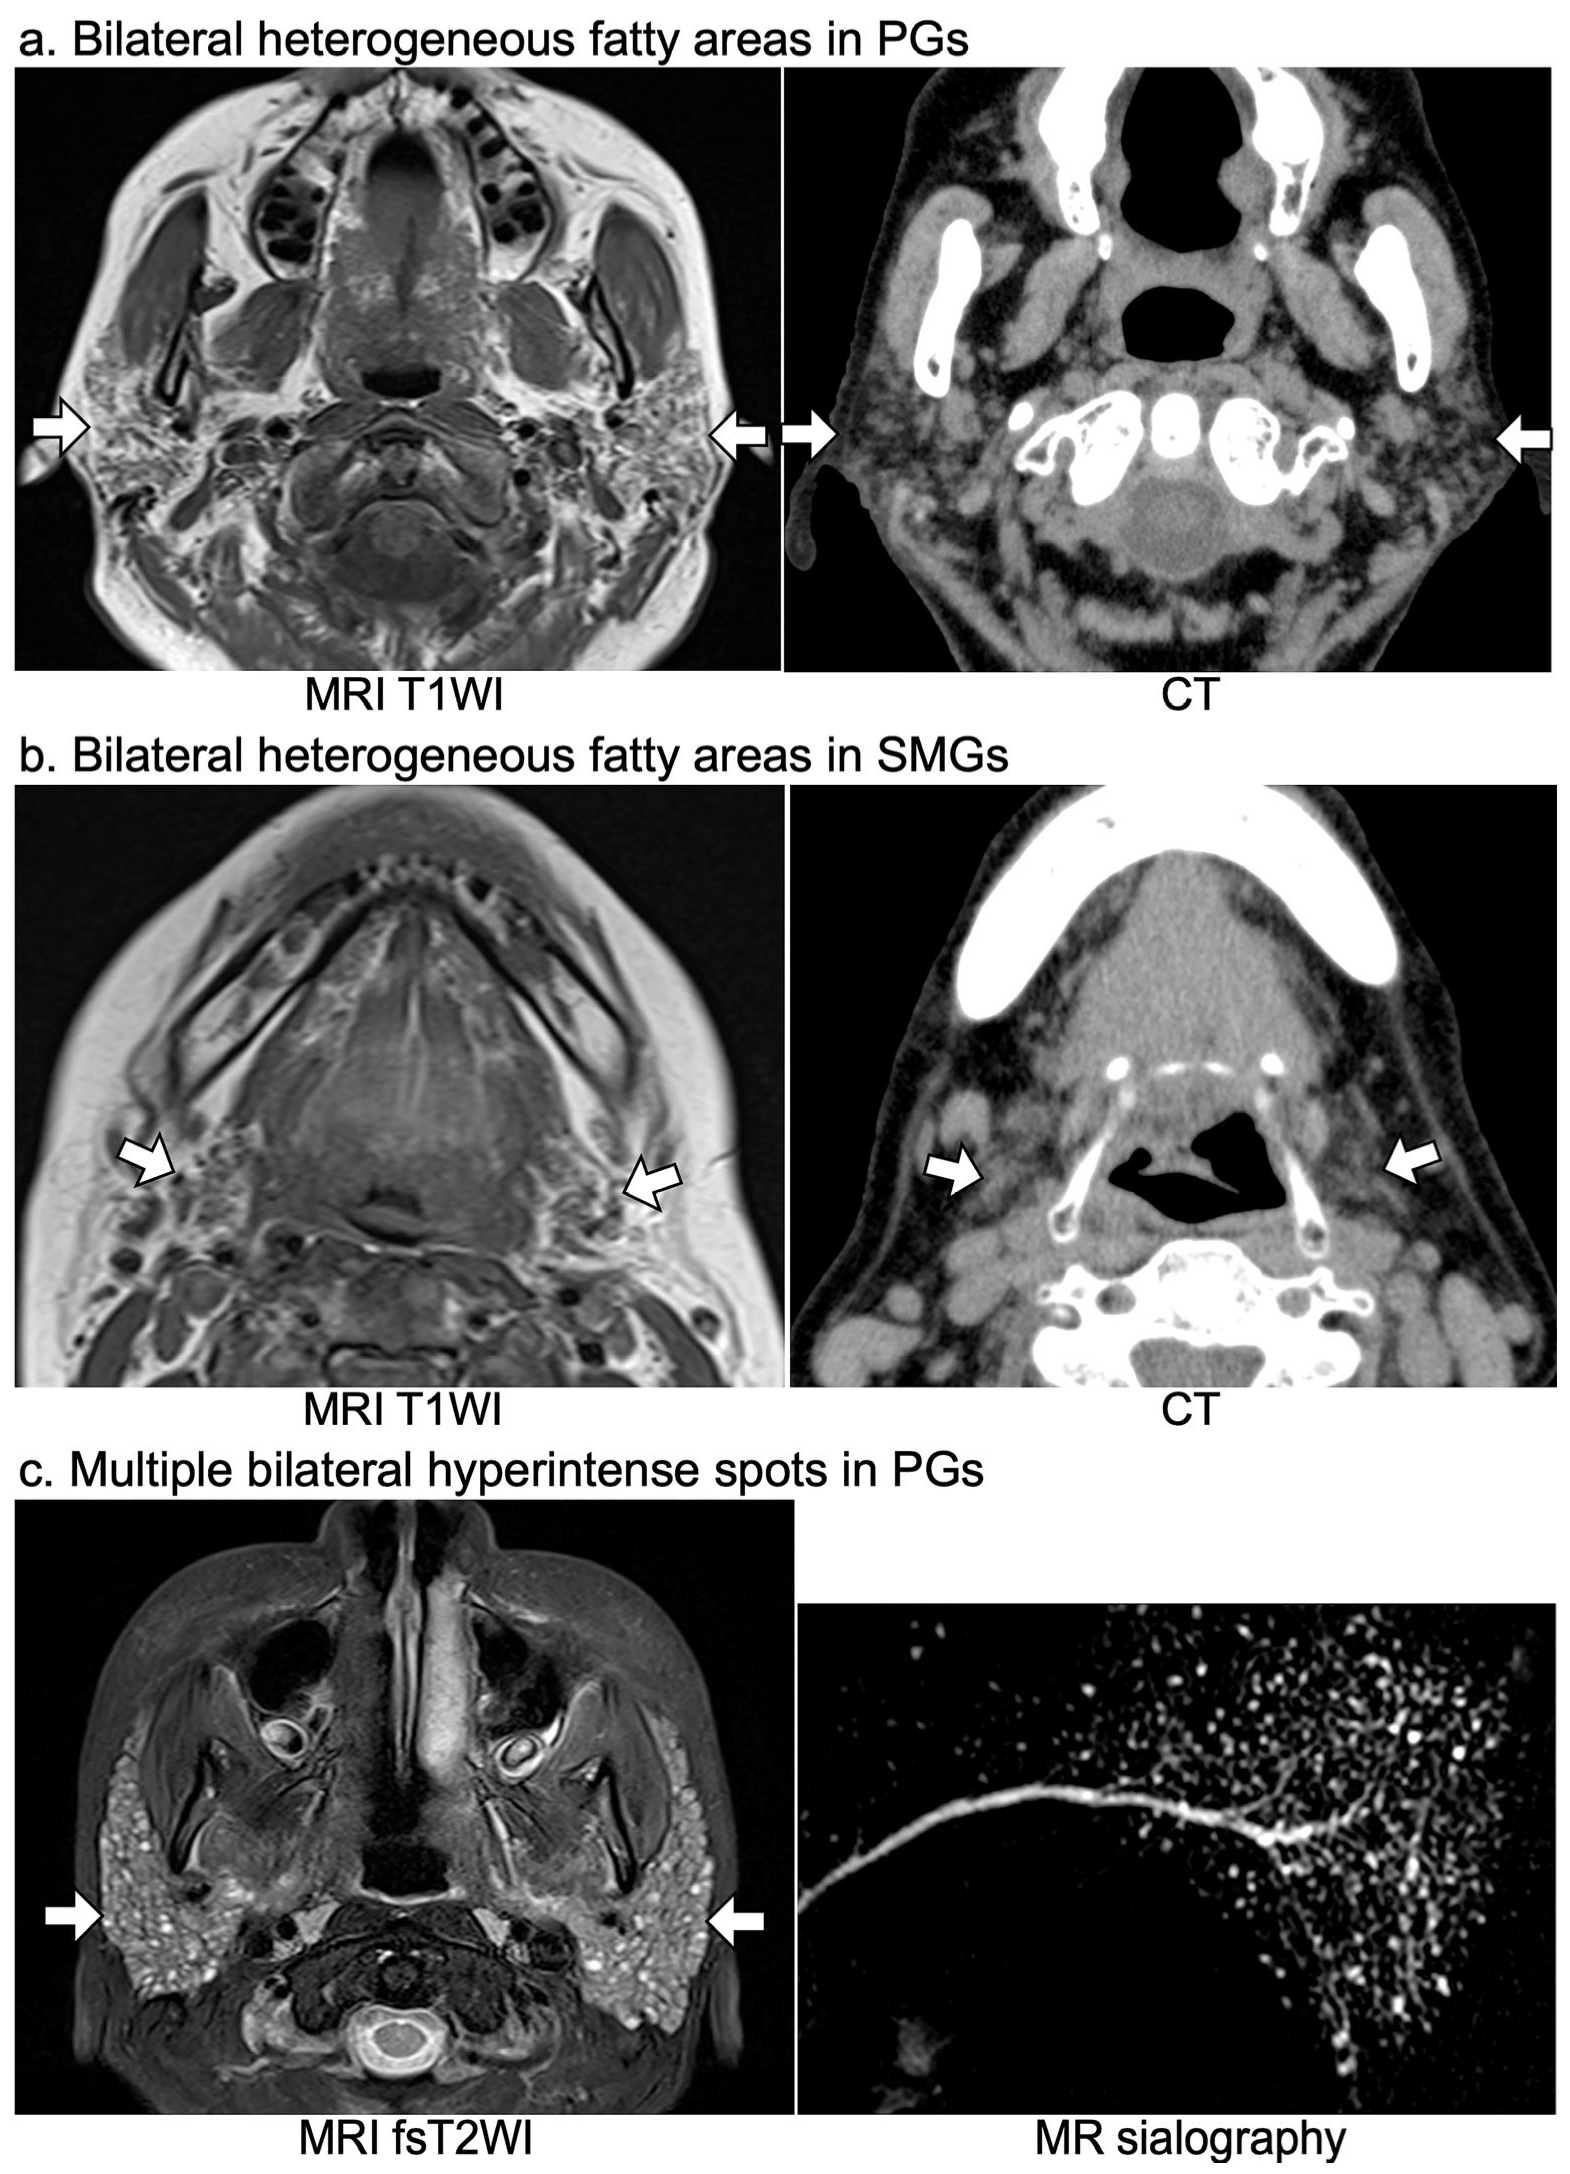

| (a) Bilateral heterogeneous fat deposition in PGs on T1WI, n (%) | 7 (58) | 2 (33) | 0 |

| (b) Bilateral heterogeneous fat deposition in SMGs on T1WI, n (%) | 7 (58) | 2 (33) | 0 |

| (c) Bilateral multiple hyperintense spots in PGs on fsT2WI or STIR, n (%) | 11 (92) | 6 (100) | 0 |

| (d) Bilateral multiple hyperintense spots in PGs on MR sialography, n (%) | 9 (9/9 = 100) * | 6 (6/6 = 100) * | 0 (0/6 = 0) * |